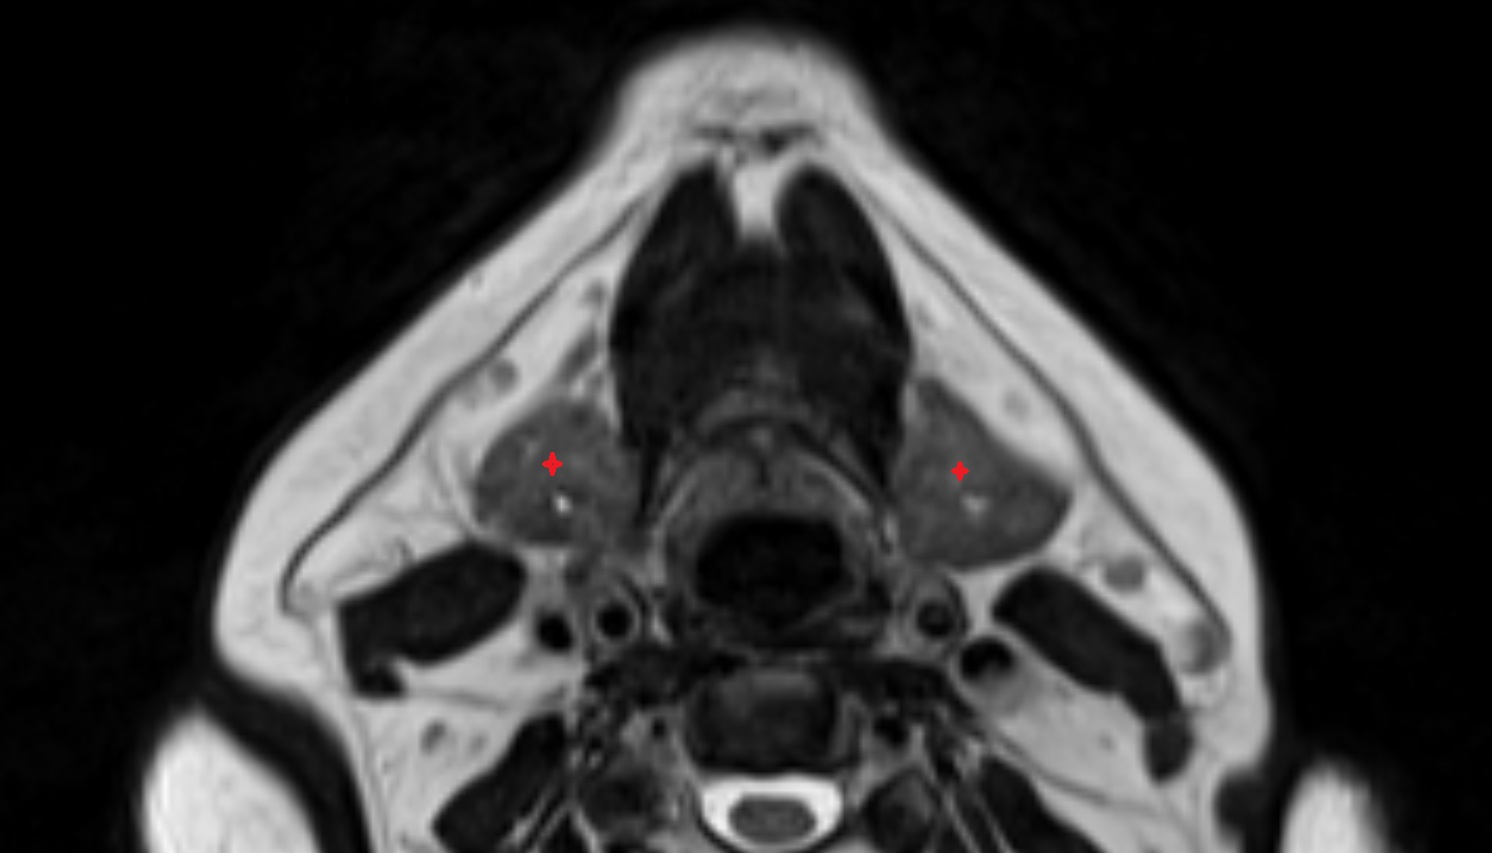

- Medial pterygoid muscle